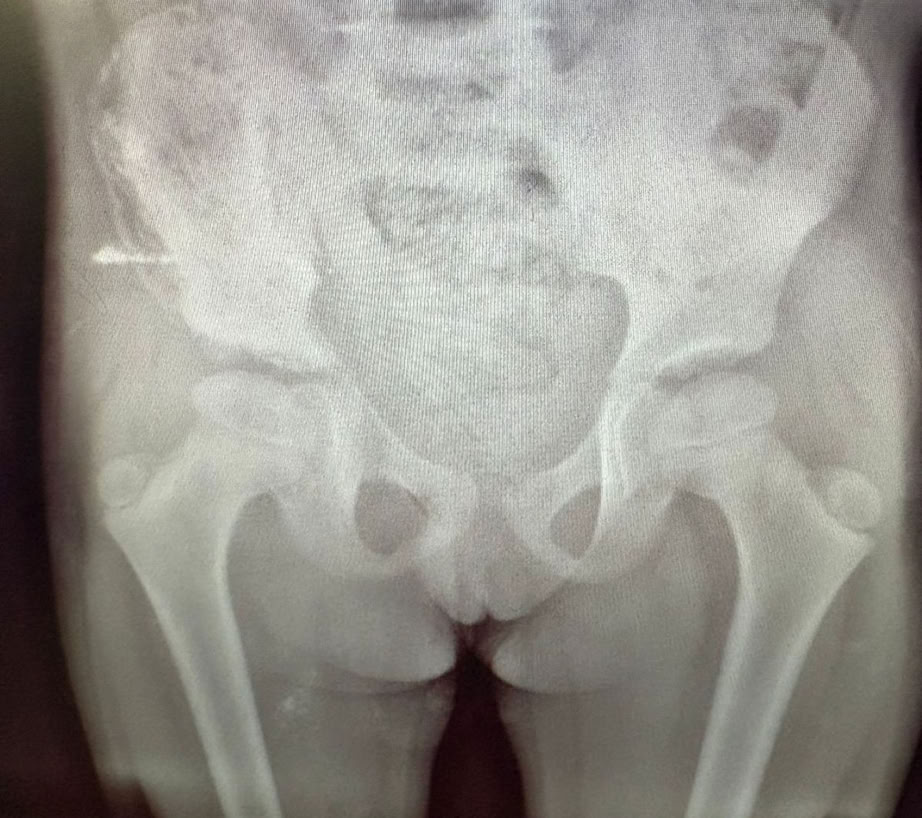

Nos encontramos dos casos de rodillas flotantes que pudimos resolver y casos de retardo de consolidación e infecciones de intervenciones previas. Igualmente las osteomielitis hematógenas y las sécales de la diabetes ocupa gran parte de la actividad de consultas de sala de curas y de las sesiones quirúrgicas.

Como en expediciones anteriores, las complicaciones de cirugías previas en otros centros, la demora de los tratamientos por el empleo de la medicina tradicional (masajes) mencionada antes, y la elevada tasa de infecciones tanto hematógenas como secundarias a diabetes mal controlada o sin tratamiento, han ocupado gran parte de nuestro trabajo.